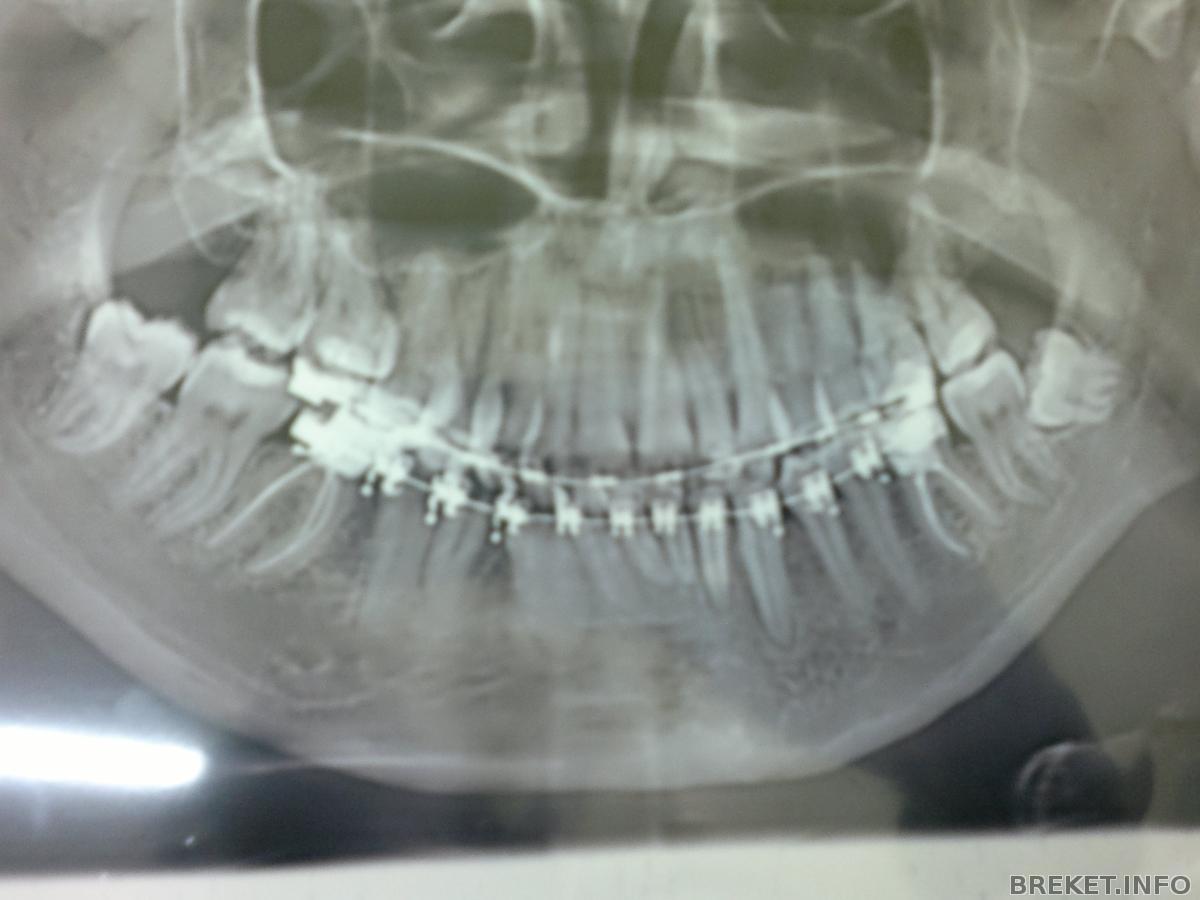

По своим новым "снимочккам" в БС, я определила

(глаз-алмаз) что за год с хвостом, ничего не изменилось

Ближе

И "панорама"